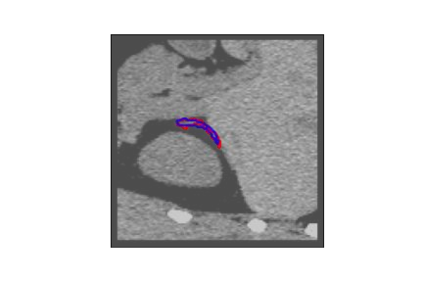

The human annotations are imperfect, especially when produced by junior practitioners. Multi-expert consensus is usually regarded as golden standard, while this annotation protocol is too expensive to implement in many real-world projects. In this study, we propose a method to refine human annotation, named Neural Annotation Refinement (NeAR). It is based on a learnable implicit function, which decodes a latent vector into represented shape. By integrating the appearance as an input of implicit functions, the appearance-aware NeAR fixes the annotation artefacts. Our method is demonstrated on the application of adrenal gland analysis. We first show that the NeAR can repair distorted golden standards on a public adrenal gland segmentation dataset. Besides, we develop a new Adrenal gLand ANalysis (ALAN) dataset with the proposed NeAR, where each case consists of a 3D shape of adrenal gland and its diagnosis label (normal vs. abnormal) assigned by experts. We show that models trained on the shapes repaired by the NeAR can diagnose adrenal glands better than the original ones. The ALAN dataset will be open-source, with 1,594 shapes for adrenal gland diagnosis, which serves as a new benchmark for medical shape analysis. Code and dataset are available at https://github.com/M3DV/NeAR.